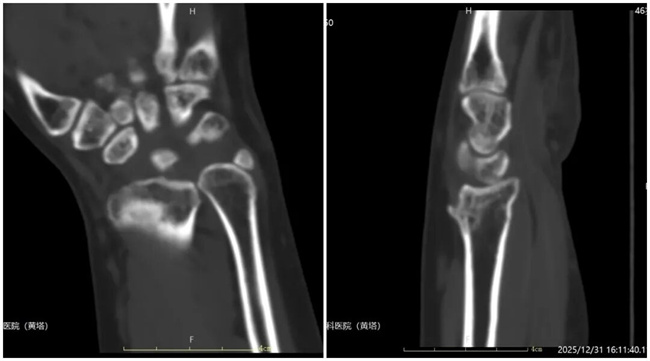

一、患者刘某某,女,46岁,患者右腕部骨折保守治疗3年,疼痛3个月,右腕背伸畸形,肩部、肘部疼痛,活动受限。为求进一步治疗,来到我院请专家会诊,通过各位专家会诊查体、查看影像资料并细致认真的分析后,诊断为:右桡骨陈旧性骨折,意见:建议截骨矫形手术。